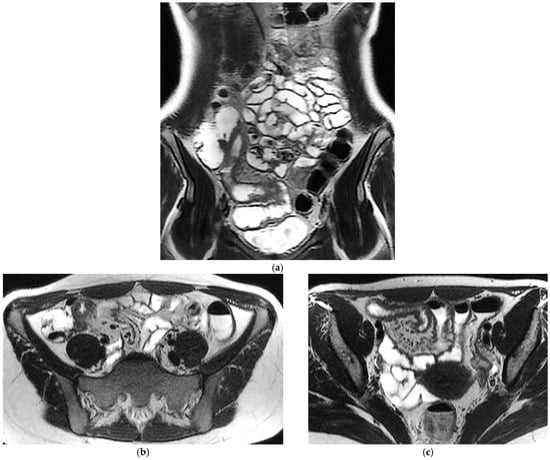

T2-weighted sequences (Figure 1a–c) are fundamental for a comprehensive morphological assessment of Crohn’s disease on both axial and coronal planes. They allow accurate definition of disease location, longitudinal extent, and severity, including evaluation of bowel wall thickening, luminal narrowing, and the presence of penetrating complications such as fistulas and abscesses at any level of the small and large bowel. These sequences are also essential for assessing extraintestinal manifestations of disease, including inflammatory changes of the surrounding mesenteric fat. Beyond structural assessment, T2-weighted imaging plays a pivotal role in the detection of inflammatory activity through the identification of mural and mesenteric oedema. In particular, Fat-Suppressed T2-weighted sequences enhance the conspicuity of oedematous tissue with a higher T2-signal, and currently represent the only imaging technique capable of directly demonstrating oedema at the level of the intestinal wall, mesenteric lymph nodes, and mesentery. Oedema is the hallmark of active inflammation, reflecting increased vascular permeability and interstitial fluid accumulation [6,12,13,14,15,16]. As such, it provides information that is complementary to mural hypervascularization observed on contrast-enhanced sequences, contributing to a more integrated and comprehensive assessment of disease activity [15,16]. Pre- and post-gadolinium–enhanced T1-weighted sequences enable detailed assessment of mucosal and transmural enhancement patterns (Figure 1d–g), which reflect bowel wall vascularity and the degree of inflammatory activity. These sequences are essential for evaluating not only the affected bowel segments, but also associated inflammatory changes in the mesentery and regional lymph nodes.

Figure 1.

20-year-old female patient with typical Crohn’s disease of the terminal ileum, evaluated with a 3T Magnet, following oral ingestion of 1500 cc of PEG solution. (a): Coronal T2w images obtained with breath-hold acquisitions show diffuse inflammatory thickening of the last ileal loop exceeding 15 cm in length. Note how the remaining loops of the small bowel wall appear normal in contrast with the affected ileal loop. (b,c): axial T2 w images showing pathological thickening of the last ileal loop. (d,e): coronal T1-weighted scan after gadolinium injection, showing marked enhancement of the ileocecal valve and terminal ileum wall. In particular, an increased mucosa enhancement is clearly visible in the terminal ileum, well distinguishable from the normal mucosa of the remaining ileal and jejunal loops. The terminal ileum is affected for at least 15–20 cm; local mesenteric hyperaemia is also observed. The entire small bowel is fully displayed (d), including jejunal and ileal loops, which appear normal with respect to the affected terminal ileum. (f,g): Axial Gd-enhanced T1-weighted images show marked concentric wall thickening and enhancement of the terminal ileum with associated mesenteric hyperaemia, due to severe inflammatory involvement. (h): Post-processing “fusion” image, in which the T2 image is merged with the post-contrast T1 image, highlighting the pathological ileal loop in 20-year-old female patient with Crohn’s disease.

This combination of structural and functional information makes MRE particularly powerful in assessing CD inflammatory activity. Increased mural thickness, hyperintensity on T2-weighted imaging, layered or transmural enhancement after contrast administration and restricted diffusion are features that correlate closely with endoscopic markers of disease severity [6,7,8,9,10,11,12,13,14,15,16,17,18,19,20]. Indeed, these imaging markers form the basis of validated scores such as the Magnetic Resonance Index of Activity (MaRIA), which is now widely accepted as a reliable surrogate for mucosal inflammation in both the ileum and colon [11,12,13,17,19,20,21]. CD activity MRI features can be further enhanced using Fusion Imaging and post-processing techniques, which can synthesize and highlight Gd-enhancement, T2-weighted and DWI at the level of the affected bowel loops (Figure 1h and Figure 2c).